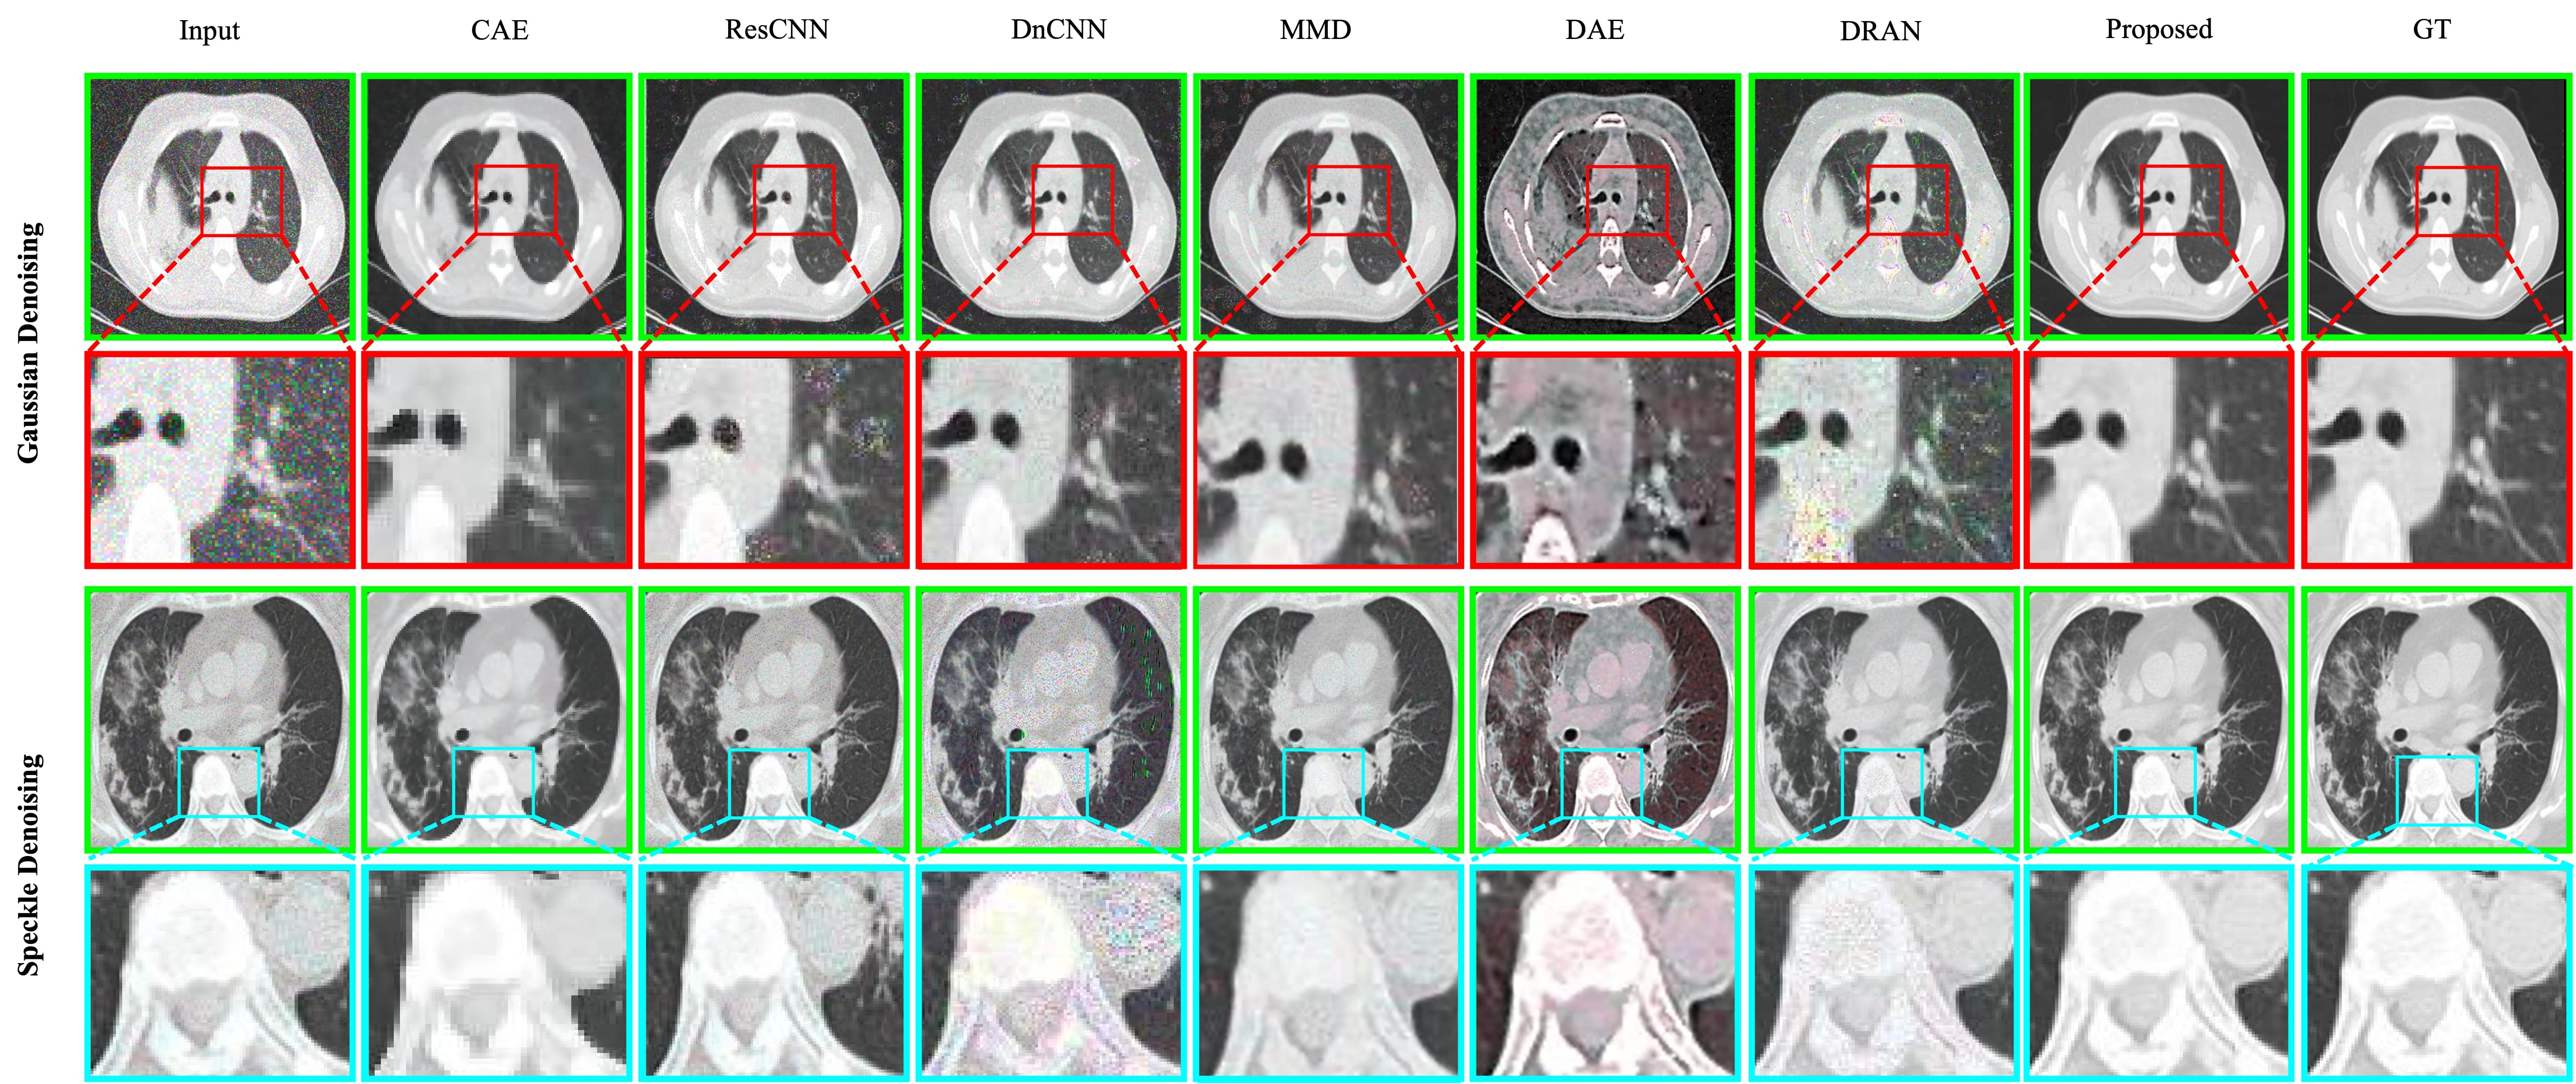

Refer to caption

Figure 1: Comparison between deep medical image denoising methods. The existing denoising methods are prone to produce smooth denoising results with visual artifacts. The top row depicts Gaussian denoising; the bottom row shows speckle denoising. In each row, Left to right: GT Image, Noisy Input, CAE [12], ResCNN [20], DnCNN [26], MMD [6], DAE [13], DRAN [1], and the proposed method.

Fig. 8 illustrates the visual comparison between the denoising methods. The proposed method can plausibly denoise the CT images as well. It can reduce noises from the CT images without illustrating any visual artifacts.

Figure 8: Qualitative comparison for CT denoising. The proposed method produces visually plausible images compared to the existing denoising methods. The top example depicts Gaussian denoising; the bottom illustrates speckle denoising. In each row, Left to right: Noisy input, CAE [12], ResCNN [20], DnCNN [26], MMD [6], DAE [13], DRAN [1] [1], proposed method, and ground truth image.